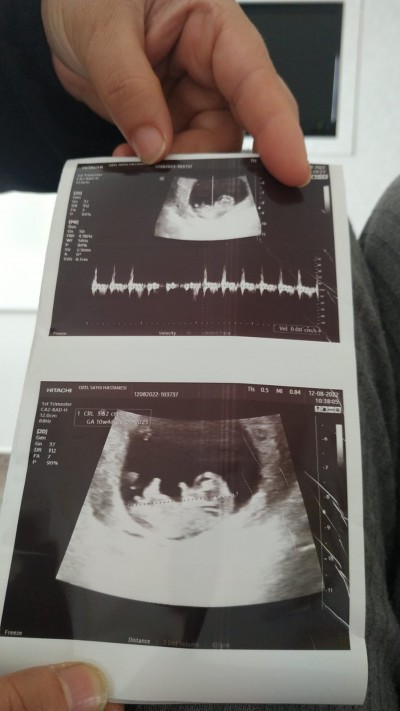

image

yesmencim benim bebiste bu

Eheheheh erkek çıktı tahmin doğru ;)))(

Valla bu özlemin tahminleri doğru çıkıyor cinsiyet sormak isteyen özleme sorsun:)